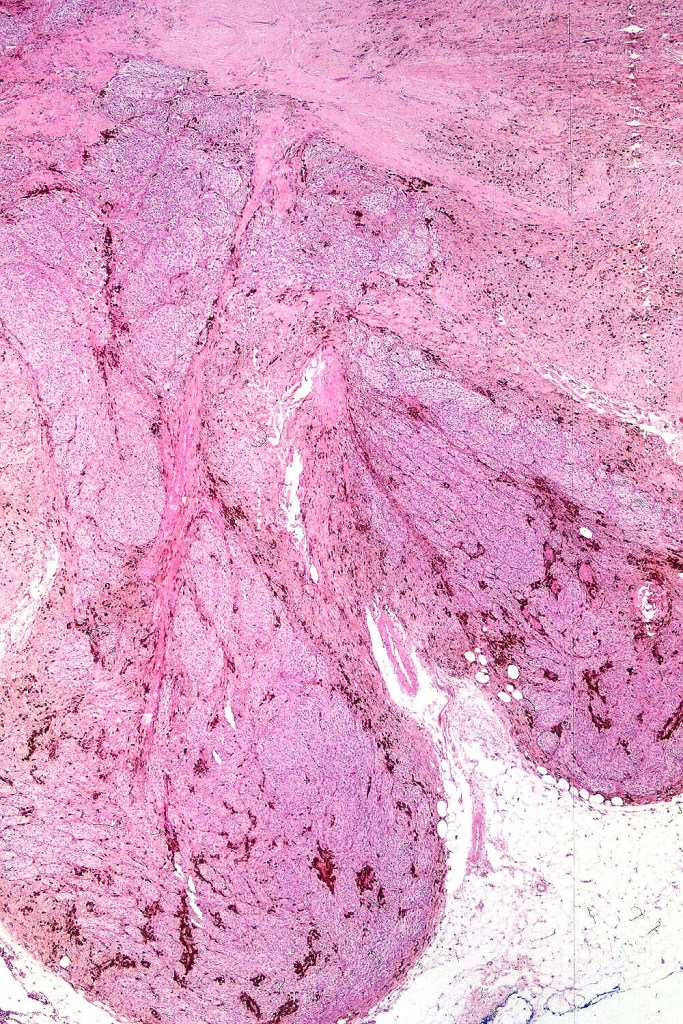

•Most characteristic is the dumbbell silhouette although a plague morphology may also be encountered

•Admixture of spindle cells, pigmented bipolar or dendritic cells & melanophages

•An alveolar pattern is characteristic particularly with clear cell nodules

•Mitoses are typically very sparse or absent

•No Necrosis or lymphovascular invasion

•Stromal fibrosis, myxoid change, vascular hyalinization with cyst formation are often seen